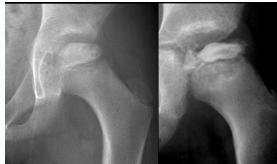

Imaging:

- Required views: AP and Frog lateral pelvis

- Key finding: Slippage of femoral epiphysis

Radiographic Examples:

Comparative views showing slipped vs. normal hip:

(Source: Apley’s System of Orthopedics and Fractures)

X-ray Diagnosis:

| View | Slipped Hip | Normal Hip |

|---|---|---|

| AP |  | - |

| Frog Lateral |  | - |